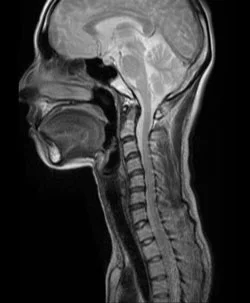

28歳女性(脳脊髄液減少症)

脳脊髄液減少症(MRI検査)

交差点を走行中、信号無視の車にぶつけられました。当初、全身に痛みがありましたが、痛みに改善がないので脳神経外科で検査、脳脊髄液減少症の診断となりました。

一年程度の鍼治療で、頭痛や、手足の症状も改善しました。脳脊髄液減少症はむち打ちの負傷直後に、水を多く飲んで安静を保つことができれば、症状の悪化を防ぐことができます。